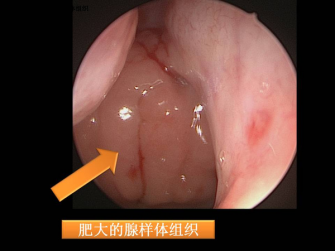

肥大的腺样体组织